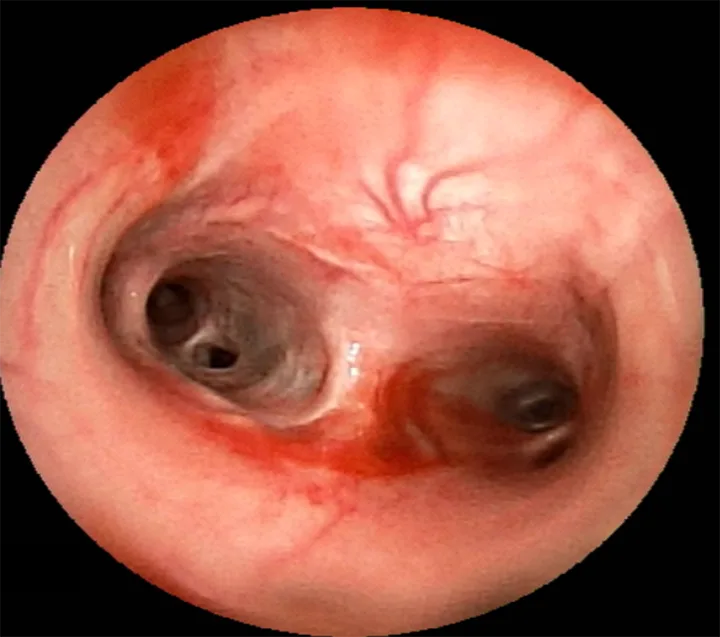

Tracheobronchoscopy can inspect mucosal surfaces of the trachea and lobar bronchi to evaluate mucosal appearance, secretions, and structural abnormalities (Figure 4). This procedure may reveal dynamic airway collapse not identified on thoracic radiography or fluoroscopy; however, anesthesia and inability to cough during the procedure may impact the amount of collapse appreciated.

Tracheobronchoscopy image of carina in a dog.

FIGURE 4

Tracheobronchoscopy image of the carina in an 11-year-old spayed Australian shepherd presented for cough. Mucosa is erythematous, and blood is present at the level of the carina, extending down the left caudal lobar bronchus.